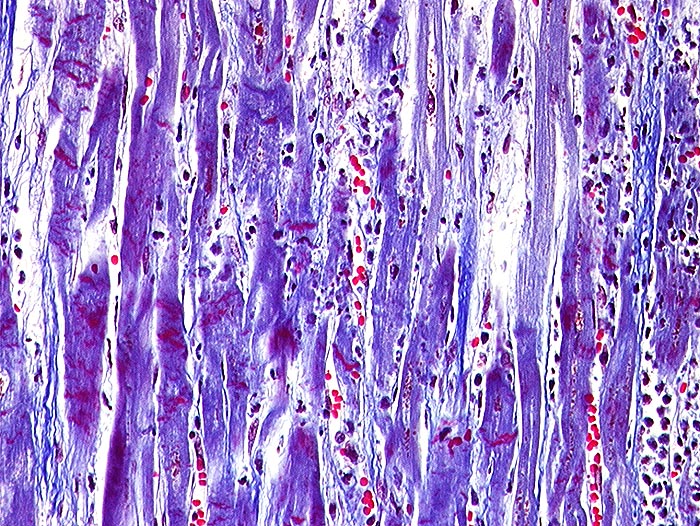

AP/ Akuter Myokardinfarkt

Akuter Myokardinfarkt

Morphologie

Pathologischer Befund